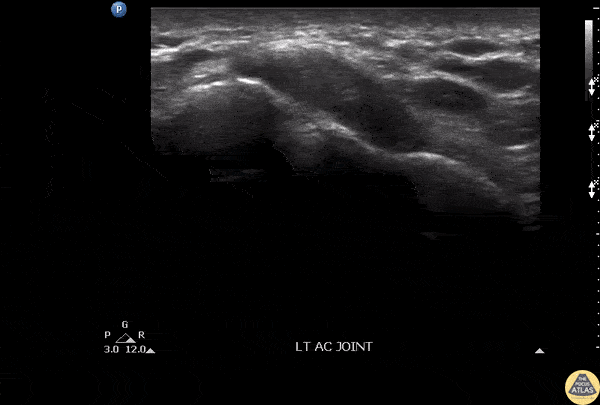

Patient presenting with shoulder pain and AC joint tenderness. Febrile to 102. POCUS revealed an AC joint effusion. Image courtesy of Robert Jones DO, FACEP @RJonesSonoEM Director, Emergency Ultrasound; MetroHealth Medical Center; Professor, Case Western Reserve Medical School, Cleveland, OH View his original post here